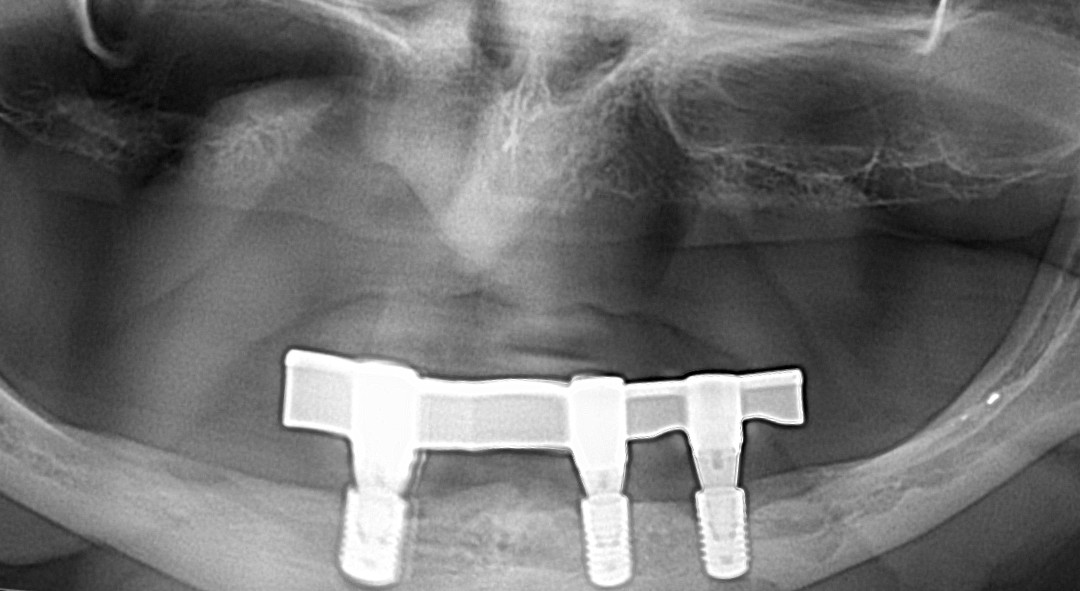

- Bar-retained dentures — A thin metal bar that follows the curve of your jaw is attached to the implants that have been placed in your jawbone. Clips or other types of attachments are fitted to the bar, the denture or both. The denture fits over the bar and is securely clipped into place by the attachment

Lower Jaw Bar Implant Overdentures

Upper Jaw Implant Overdentures on 3 Implants